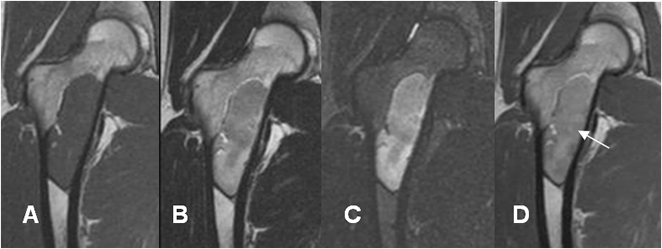

Fig 103 B. Displasia fibrosa.

A: RM coronal en T1, B: RM coronal en T2, C: RM coronal en STIR y D: RM coronal en T1 con contraste. Igual paciente anterior. Se identifica imagen ovalada e hipointensa en T1 y T2, hiperintensa en STIR y que realza con el contraste (Flecha). La lesión es hipointensa en T2, por el alto contenido fibroso.